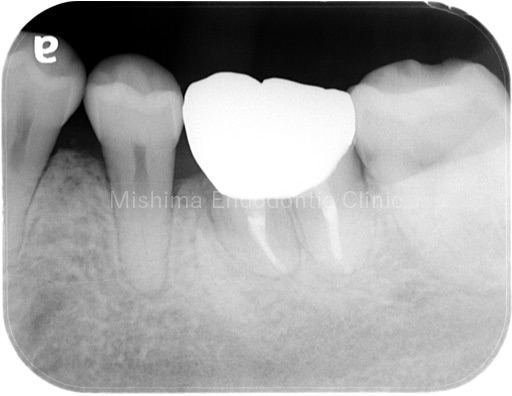

After

| 治療内容 | 矯正治療の既往あり。CBCTから侵襲性歯頚部吸収、歯髄診査により歯髄壊死と診断。垂直性骨欠損の改善と吸収部の封鎖を補綴で行うべく、根管治療後にアップライトを行った。術前には7mmのポケットを認めたが、術後は全周ポケット2mmで歯槽骨頂の水平性が獲得でき、経過は良好。 |